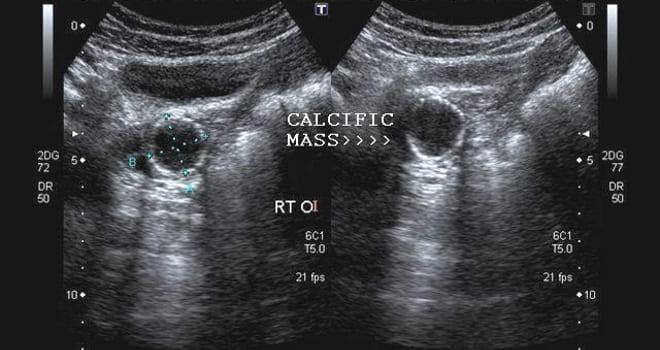

Кальцинаты в яичниках, выявленные при ультразвуковом исследовании, вызывают интерес и порой беспокойство как у пациентов, так и у врачей. Эксперты отмечают, что наличие кальцинатов может свидетельствовать о различных процессах в организме. В большинстве случаев это не является признаком серьезного заболевания, а может быть результатом старения тканей или предшествующих воспалительных процессов. Однако важно учитывать, что кальцинаты могут также указывать на наличие опухолей, как доброкачественных, так и злокачественных. Поэтому специалисты рекомендуют проводить дополнительные исследования для уточнения диагноза. Важно, чтобы пациент не паниковал, а обсудил результаты УЗИ с врачом, который сможет дать рекомендации по дальнейшим действиям и необходимым обследованиям.

- Ультразвуковое исследование (УЗИ) позволяет обнаружить кальцинаты в яичниках. Существует три метода проведения УЗИ, из которых трансвагинальный считается наиболее информативным, так как введение датчика во влагалище дает возможность получить детальную информацию о состоянии половых органов;